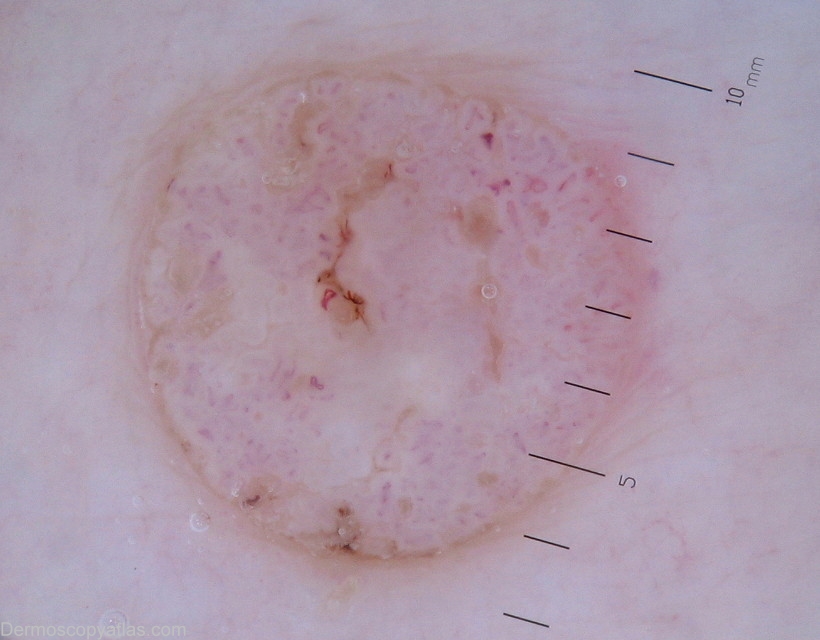

Site: Back

Diagnosis: Inkspot lentigene

Age: 66

Description: Dermoscopy -Right scapula area.Bizzare,black pigment network.

History of multiple non melanoma skin cancers.

Images of seborrheic keratosis was also illustrated along with inkspot(reticulated) lentigo.